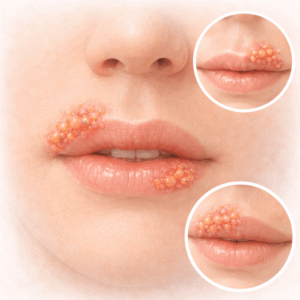

Cât durează episoadele de herpes și cum să le gestionezi?

A avea o eruptie de herpes este ca și cum ai avea…

Citește articolul

Cum să scapi rapid de herpesul bucal cu Valaciclovir

Herpesul bucal poate apărea în cele mai nepotrivite momente, lăsându-te frustrat și…

Citește articolul

Valaciclovir și herpesul bucal: Ce ajută cu adevărat?

Începe chestionarul